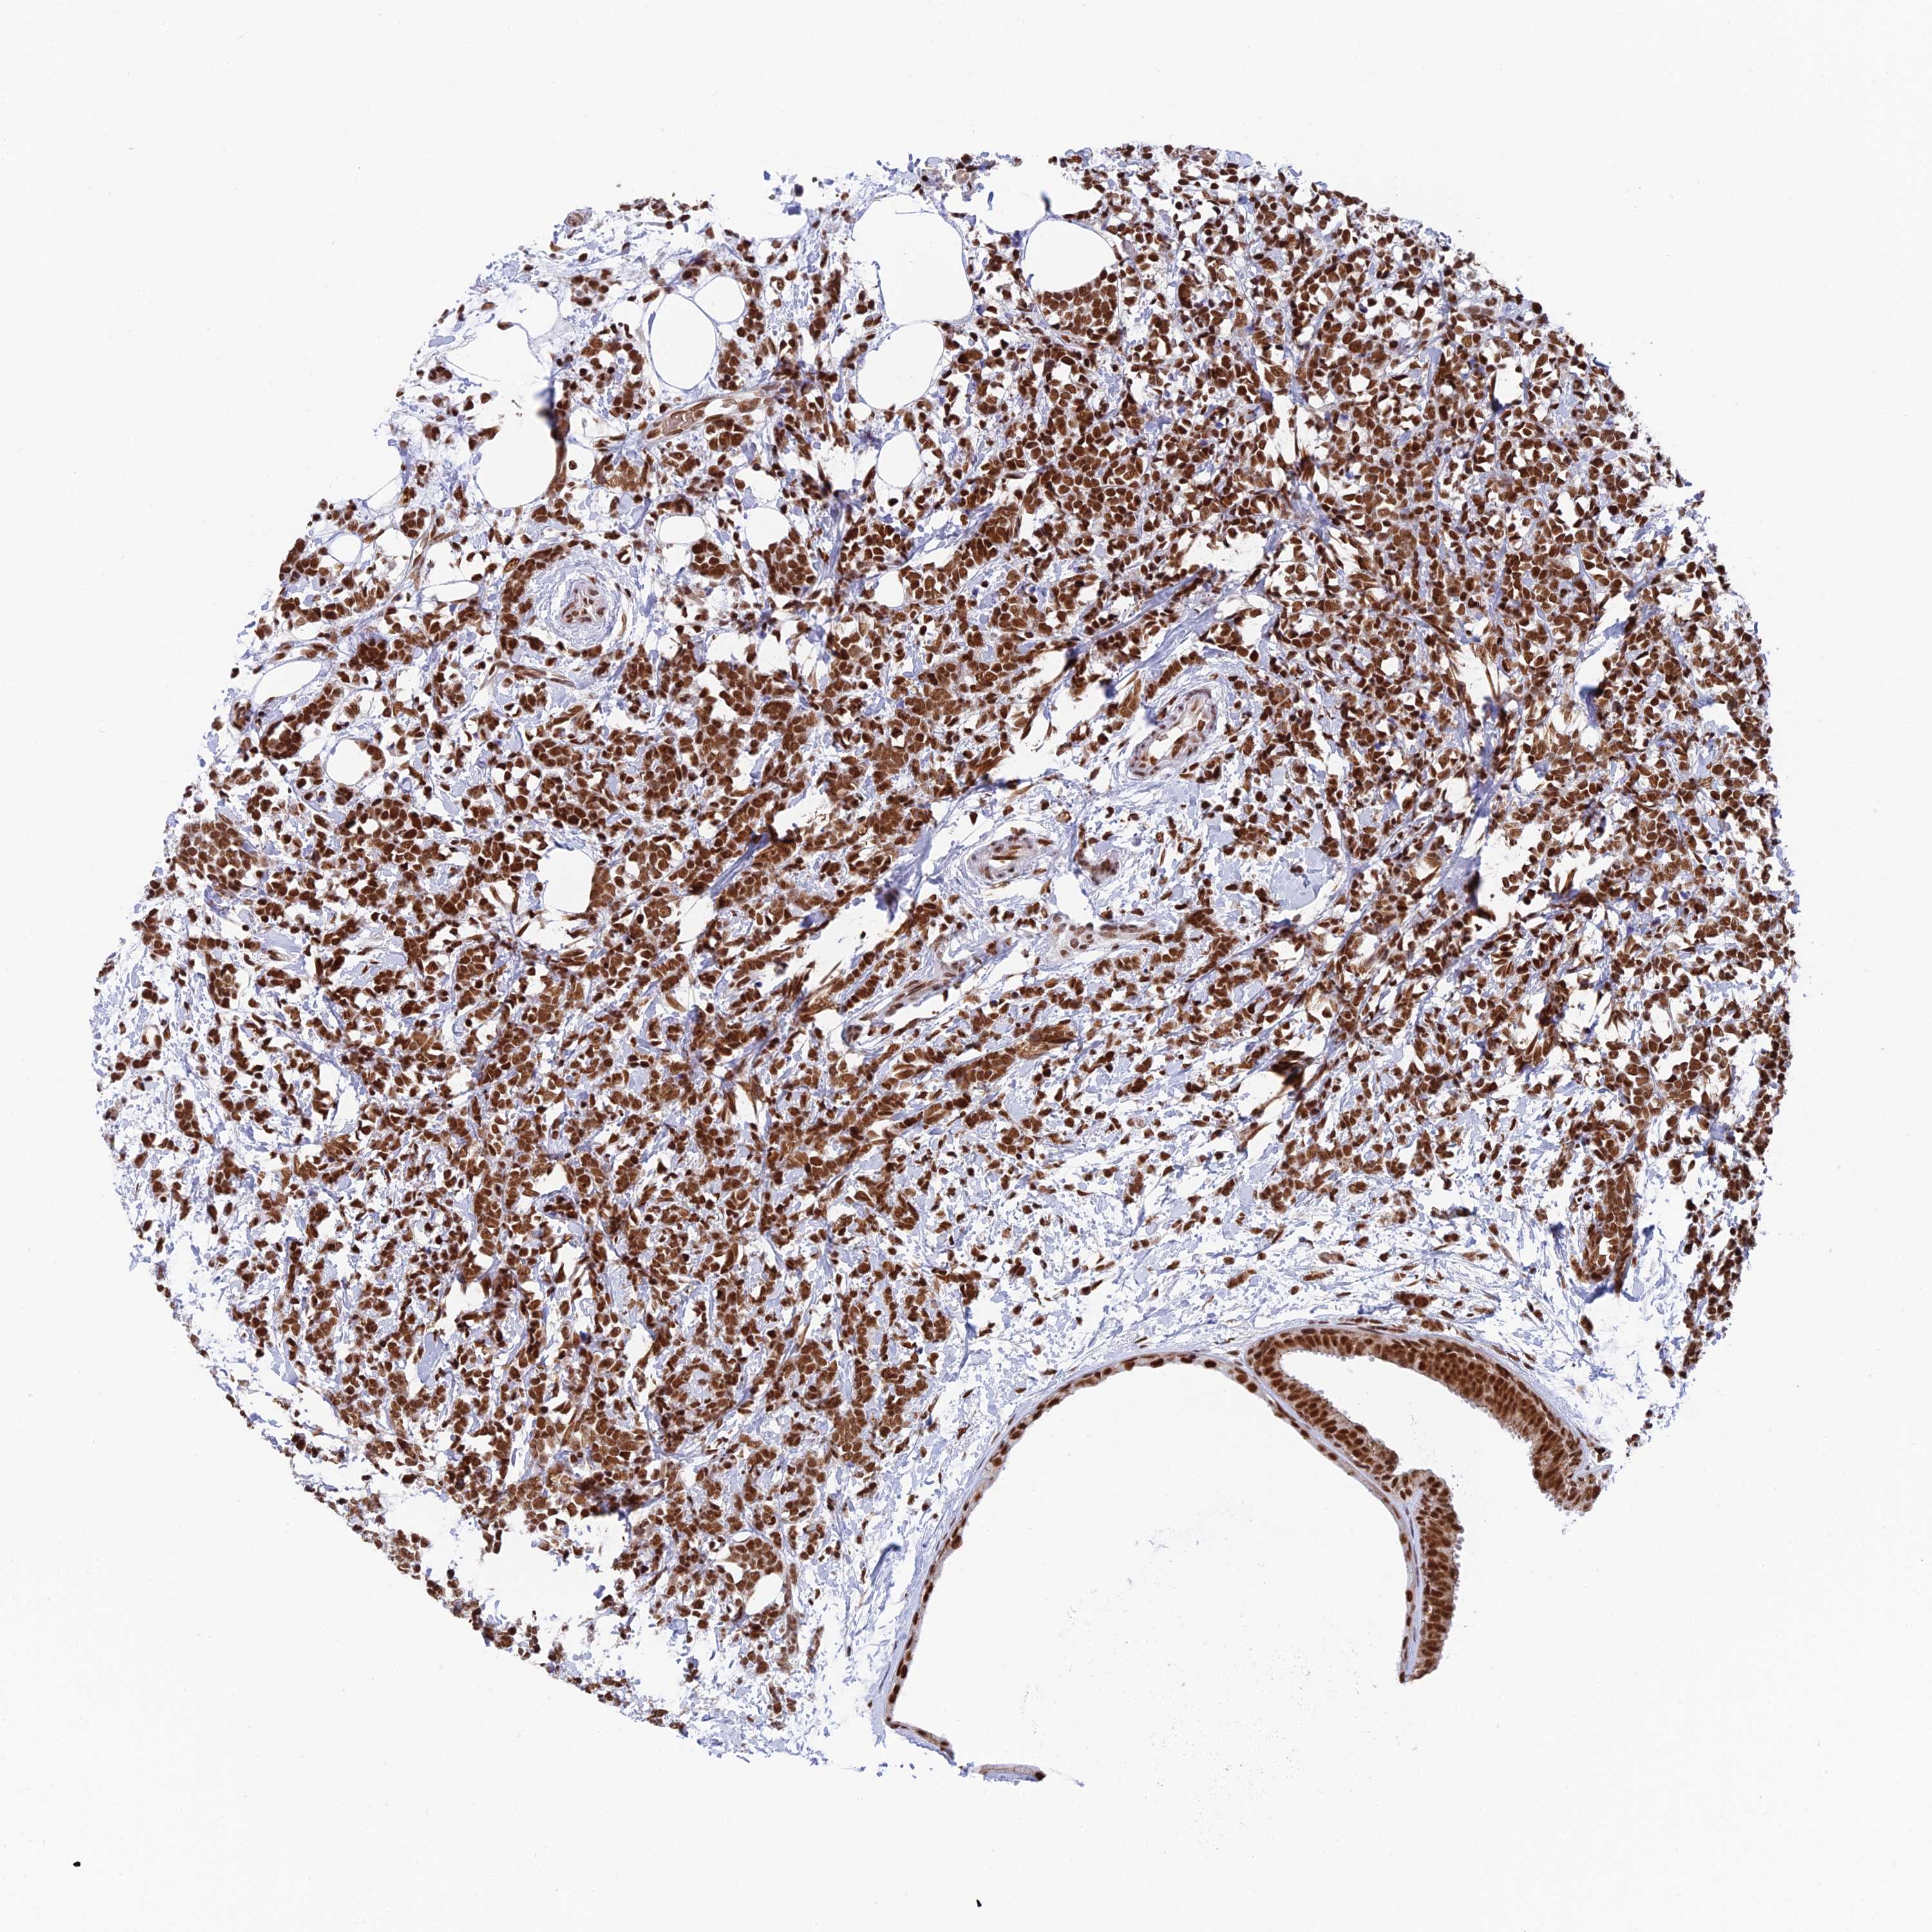

BRCA TCGA BRCA VALIDATION PROTEIN EXPRESSION